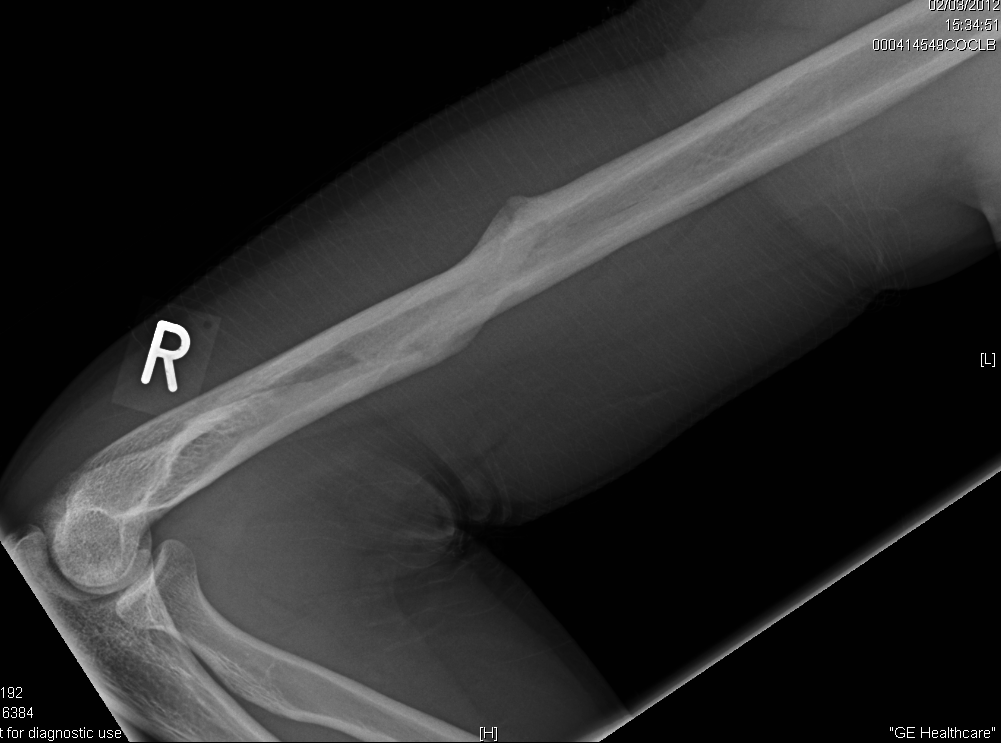

Spiral Humeral Shaft Fracture Spiral Humerus Break a spiral fracture (a.k.a. — you may develop a spiral fracture pattern in the humerus due to some twisting injuries. You develop it in the shaft of the humerus when you. there are two types of humerus fractures based on the location of the break (s). Trauma from a fall or accident are often the cause of. Spiral Humerus Break.

Broken Humerus Xray Showing Compound Spiral Stock Photo 666295192 Spiral Humerus Break — a spiral fracture is a bone fracture that occurs when a long bone is broken by a twisting force. Trauma from a fall or accident are often the cause of this type of fracture. Spiral fractures typically affect long bones (those that are longer than they are wide) found in your arms, legs, hands, and feet. a. Spiral Humerus Break.

Humeral fracture spiral midshaft Image Spiral Humerus Break Trauma from a fall or accident are often the cause of this type of fracture. This type of fracture results from a twisting force on the bone during an injury. a spiral fracture, also known as torsion fracture, is a type of complete fracture that occurs due to a rotational, or twisting, force. You develop it in the shaft. Spiral Humerus Break.